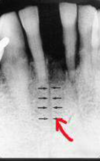

98

identify the anatomical structure below.

nutrient canals